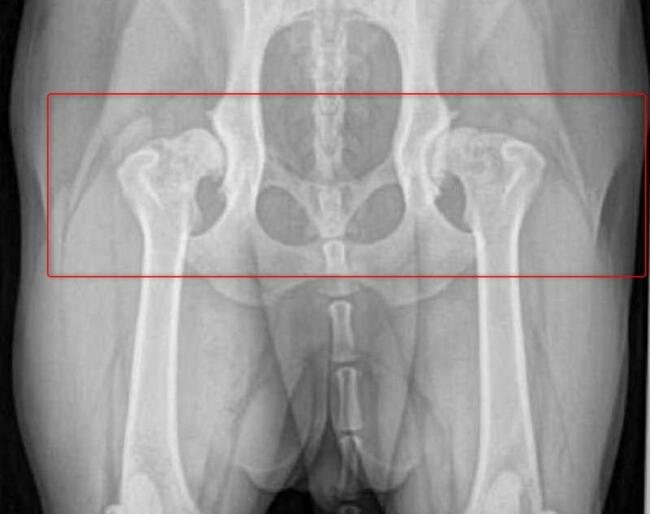

Mój ukochany Max ma dysplazje stawów tylne nogi oraz biodra odmawiają posłuszeństwa. Dotychczas starałam się finansować każdą wizytę, operację, zabiegi i rehabilitację. Niestety, nadszedł moment, gdy zostałam postawiona pod ścianą. Z osoby wspomagającej, mój przyjaciel i ja staliśmy się potrzebującymi.

Niestety stopień zwyrodnienia stawów i poziom zaawansowania choroby kwalifikuje Maxa na operację wstawienia endoprotez w obu biodrach, których koszt mimo moich oszczędności przekracza moje możliwości